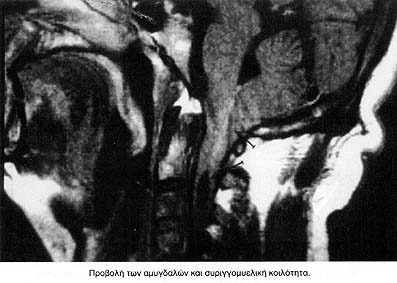

Από τις νευροαπεικονιστικές μεθόδους η αξονική τομογραφία εγκεφάλου με εμπλουτισμό, έδειξε εκτασία της αριστερής σπονδυλικής ενώ η τομογραφία με μαγνητικό συντονισμό έδειξε:

γ. Συριγγομυελική κοιλότητα ισοϋψώς του επιπέδου του Α2 έως Α4, με έκταση 33 χιλ. προκαλώντας ελαφρά διόγκωση του νωτιαίου μυελού.

Τα ανωτέρω ευρήματα συνηγορούν υπέρ δυσπλασίας Arnold-Chiari τύπου Ι.